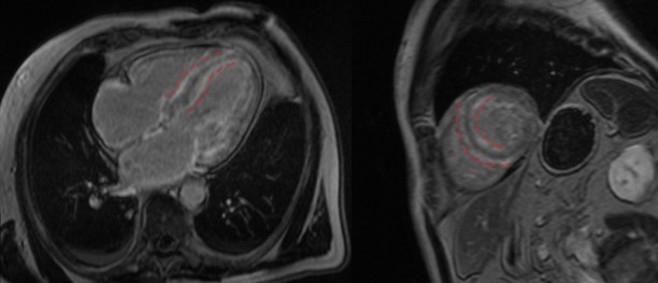

LGE in MRI of the heart in ATTR-amyloidosis. A subendocardial accumulation of the contrast agent in IVS on both the LV and RV (dotted red lines).